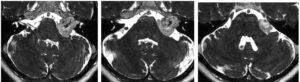

53歳男性、進行する左片麻痺で発症した右insular gliomaを手術しました。背景に右側頭葉から両側前頭葉に広がるgrade 2 gliomaがあると推定されます。画像的には最近導入されたメチオニンPET(アキュミン)が極めて役に立ちました。シルビウス裂はtightでしたがなんとか開けて、術中CTと5-ALAを用いて摘出しました。術後麻痺の悪化や他の神経学的悪化なく経過しています。